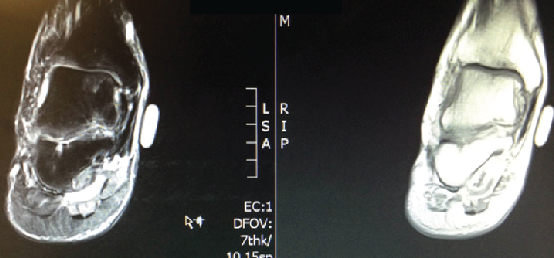

The patient’s physical exam was significant for tenderness to palpation across the ankle joint with pain on active and passive range of motion. He was neurovascularly intact. The patient had clinical and radiographic evidence of a 1.4 cm osteochondritis dissecans as shown in an MRI from March 2011.